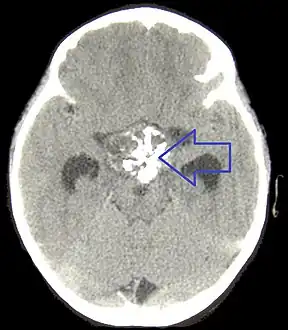

A physician can conduct a few scans and tests to diagnose a person with craniopharyngioma.[19] High-resolution magnetic resonance imaging (MRI) is commonly used as a diagnostic tool; however, computer tomography (CT) remains the gold standard imaging choice for craniopharyngioma diagnosis as it can detect the severity of the calcification within the tumour.[20]

In some cases, a powerful 3T (Tesla) MRI scanner can help define the location of critical brain structures affected by the tumor. The histologic pattern consists of nesting of squamous epithelium bordered by radially arranged cells. It is frequently accompanied by calcium deposition and may have a microscopic papillary architecture. A computed tomography (CT) scan is also a good diagnostic tool, as it detects calcification in the tumor.[21]

In the adamantinomatous type, calcifications are visible on neuroimaging and are helpful in diagnosis.

CT scan showing a craniopharyngioma